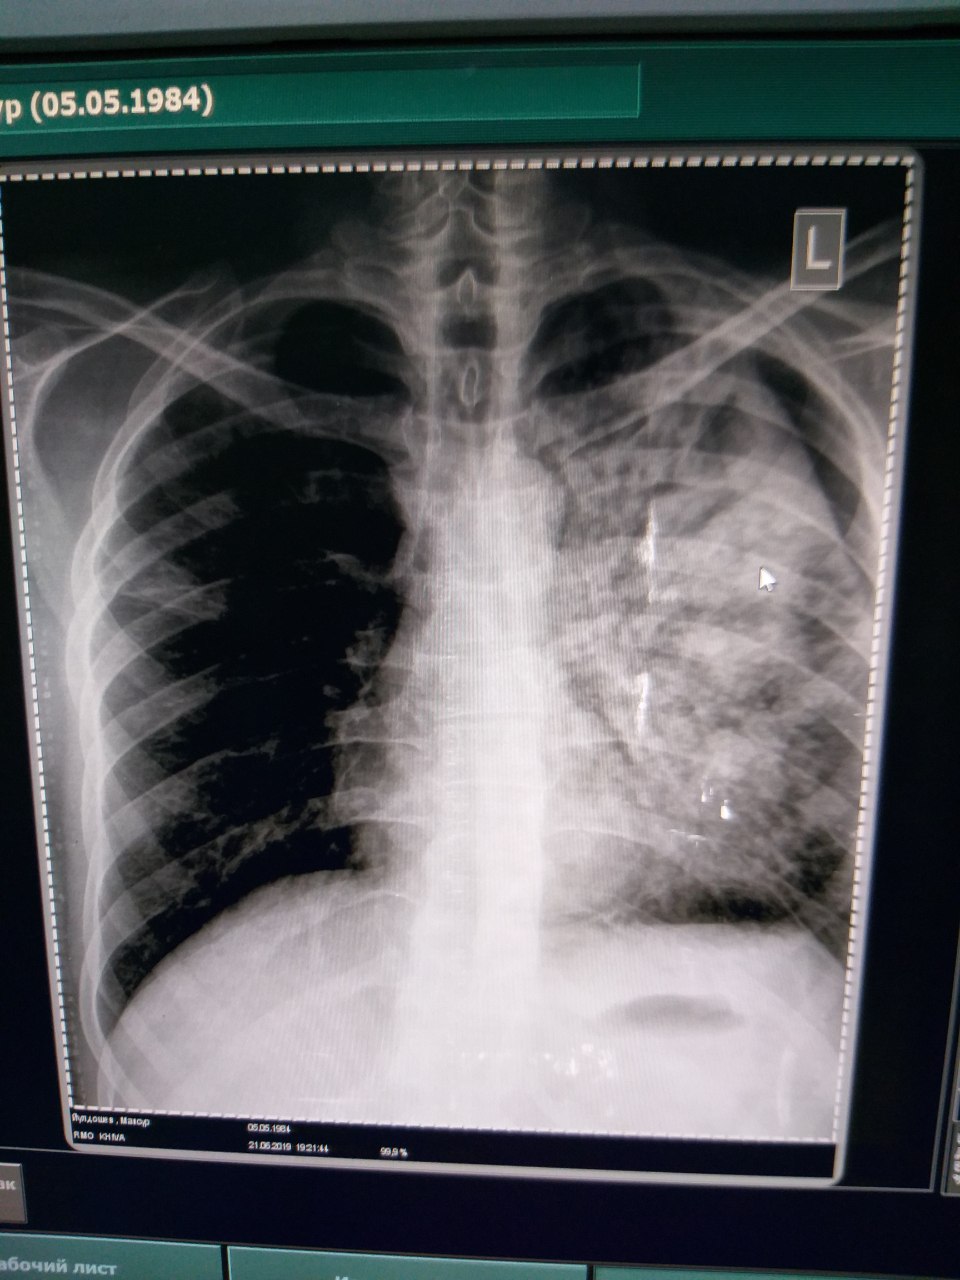

Товарищи что там 😧

Не инфаркт?

Это что?

Операции были на легких?

АД 70/30. Темп. 35,

Экссудат был

Это артефакты кассеты

КТ нету. рентген есть только...

Инфаркт пневмония обширная. Но нужно кт

Пневмония

Инфаркт?